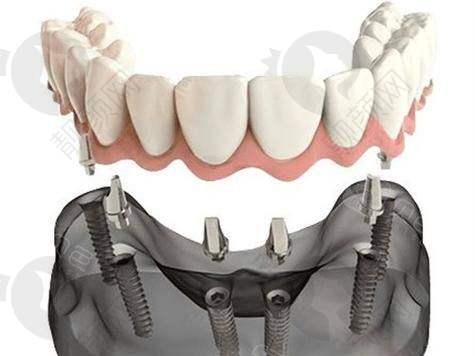

给我看牙的就是黎强院长。黎院长人特别和蔼可亲,他先仔细地给我检查了牙齿,又问了我的一些生活习惯和需求。然后跟我详细地解释了种植牙的原理、过程和注意事项。他说我这种半口牙齿缺失的情况,做半口速齿种植牙挺合适的。

我更关心的还是价格问题。黎院长给我算了一下费用,说做半口速齿种植牙,总共下来大概5万。我当时一听,简直不敢相信自己的耳朵。我之前了解过,一般半口种植牙至少得七八万,甚至更贵,这5万的价格对我来说真的太划算了。

回家后的几天,牙齿有点轻微的肿胀和疼痛,不过都在能忍受的范围内。按照黎院长说的注意事项去做,修复得还挺快。大概过了一个月左右,种植体就和牙槽骨结合得差不多了,然后又去安装了牙冠。